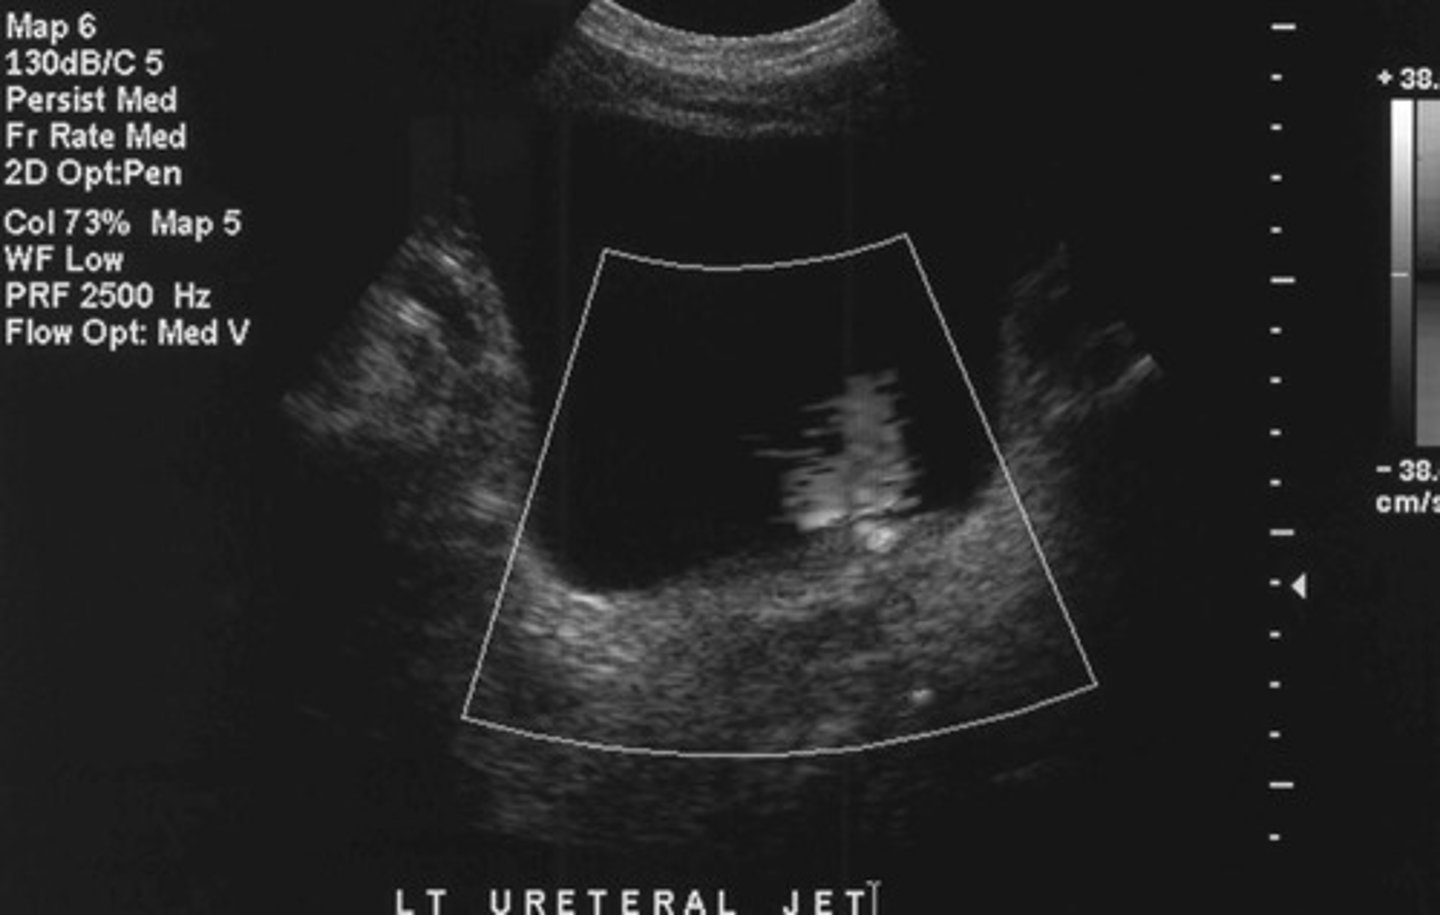

Urethral jet

What does this image show

<p>What does this image show</p>

Want to determine if the stone is completely or just partially obstructing an ureter

Why do you ALWAYS want to asses a urine jet when you find a stone in the ureter

Ureteral jets (is it fully or partially obstructive?)

What else should you assess if you identify obstructive hydro

78

New cards

The treatment/how fast we need to treat the patient (if fully obstructive may be more emergent)

Why do you need to determine if an obstruction in the collecting system is fully obstructive